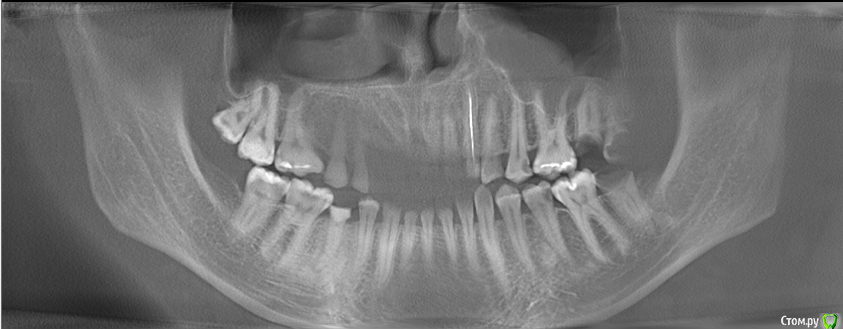

veraprok Опубликовано 25 июня, 2015 Поделиться Опубликовано 25 июня, 2015 У сына зубы разрушаются безболезненно. При этом на зубах какие-то белые "шапочки", которые видны на снимках, которые я прикрепила к сообщению.Зуб разрушается так, как будто кто-то снимает с него всю эмаль, оставляя только то, что в середине.Один только раз у него была боль, но болел висок, и он обращался к невропатологу, и его лечили от невралгии лицевого нерва, а это был зуб верхней челюси, когда его пролечили, боль прошла.Но во всех остальных случаях он не замечает разрушения зубов, так как зуб может быть разрушен до основания, но не болит.У него проблемы со щитовидной железой. Не знаю, влияет ли это, но на всякий случай сообщаю.Что это и как с этим бороться? Потому что разрушение всех зубов идет быстрыми темпами., и я боюсь, что он потеряет все зубы. Ссылка на комментарий

faity Опубликовано 25 июня, 2015 Поделиться Опубликовано 25 июня, 2015 белые шапочки на снимках это и есть эмаль, при болезнях щитовидной железы бывают проблемы с зубами,но это индивидуально. не надо ждать пока заболят зубы, посещайте стоматолога раз в полгода или чаще, делайте диагностические снимки и обследования, и брекеты поставьте. тогда и сустав перестанет болеть и зубы крошиться, гипернагрузка это плохо Ссылка на комментарий

veraprok Опубликовано 25 июня, 2015 Автор Поделиться Опубликовано 25 июня, 2015 Да нет же, я такого никогда не видела - чтобы эмаль была нестественно белого цвета! Причем, если зуб "помечен" такой шапочкой, но еще не начал разрушаться - это уже как метка, что очень скоро разрушится.Извините, я ждала конструктивного ответа, а не общих слов. Ссылка на комментарий

veraprok Опубликовано 25 июня, 2015 Автор Поделиться Опубликовано 25 июня, 2015 Целых три фото прикреплено!!! Вы разве их не видите?! Ссылка на комментарий

faity Опубликовано 25 июня, 2015 Поделиться Опубликовано 25 июня, 2015 Целых три фото прикреплено!!! Вы разве их не видите?! я вижу 3 рентгеновских снимка и ни одной фотографии!!! вы разве не прочитали то, что вам написал я и мой коллега?! Ссылка на комментарий

Scrabble Опубликовано 25 июня, 2015 Поделиться Опубликовано 25 июня, 2015 Белые шапочки на рентгене-это эмаль. Сфотографируйте зубы в полости рта. Сколько лет сыну? Ссылка на комментарий